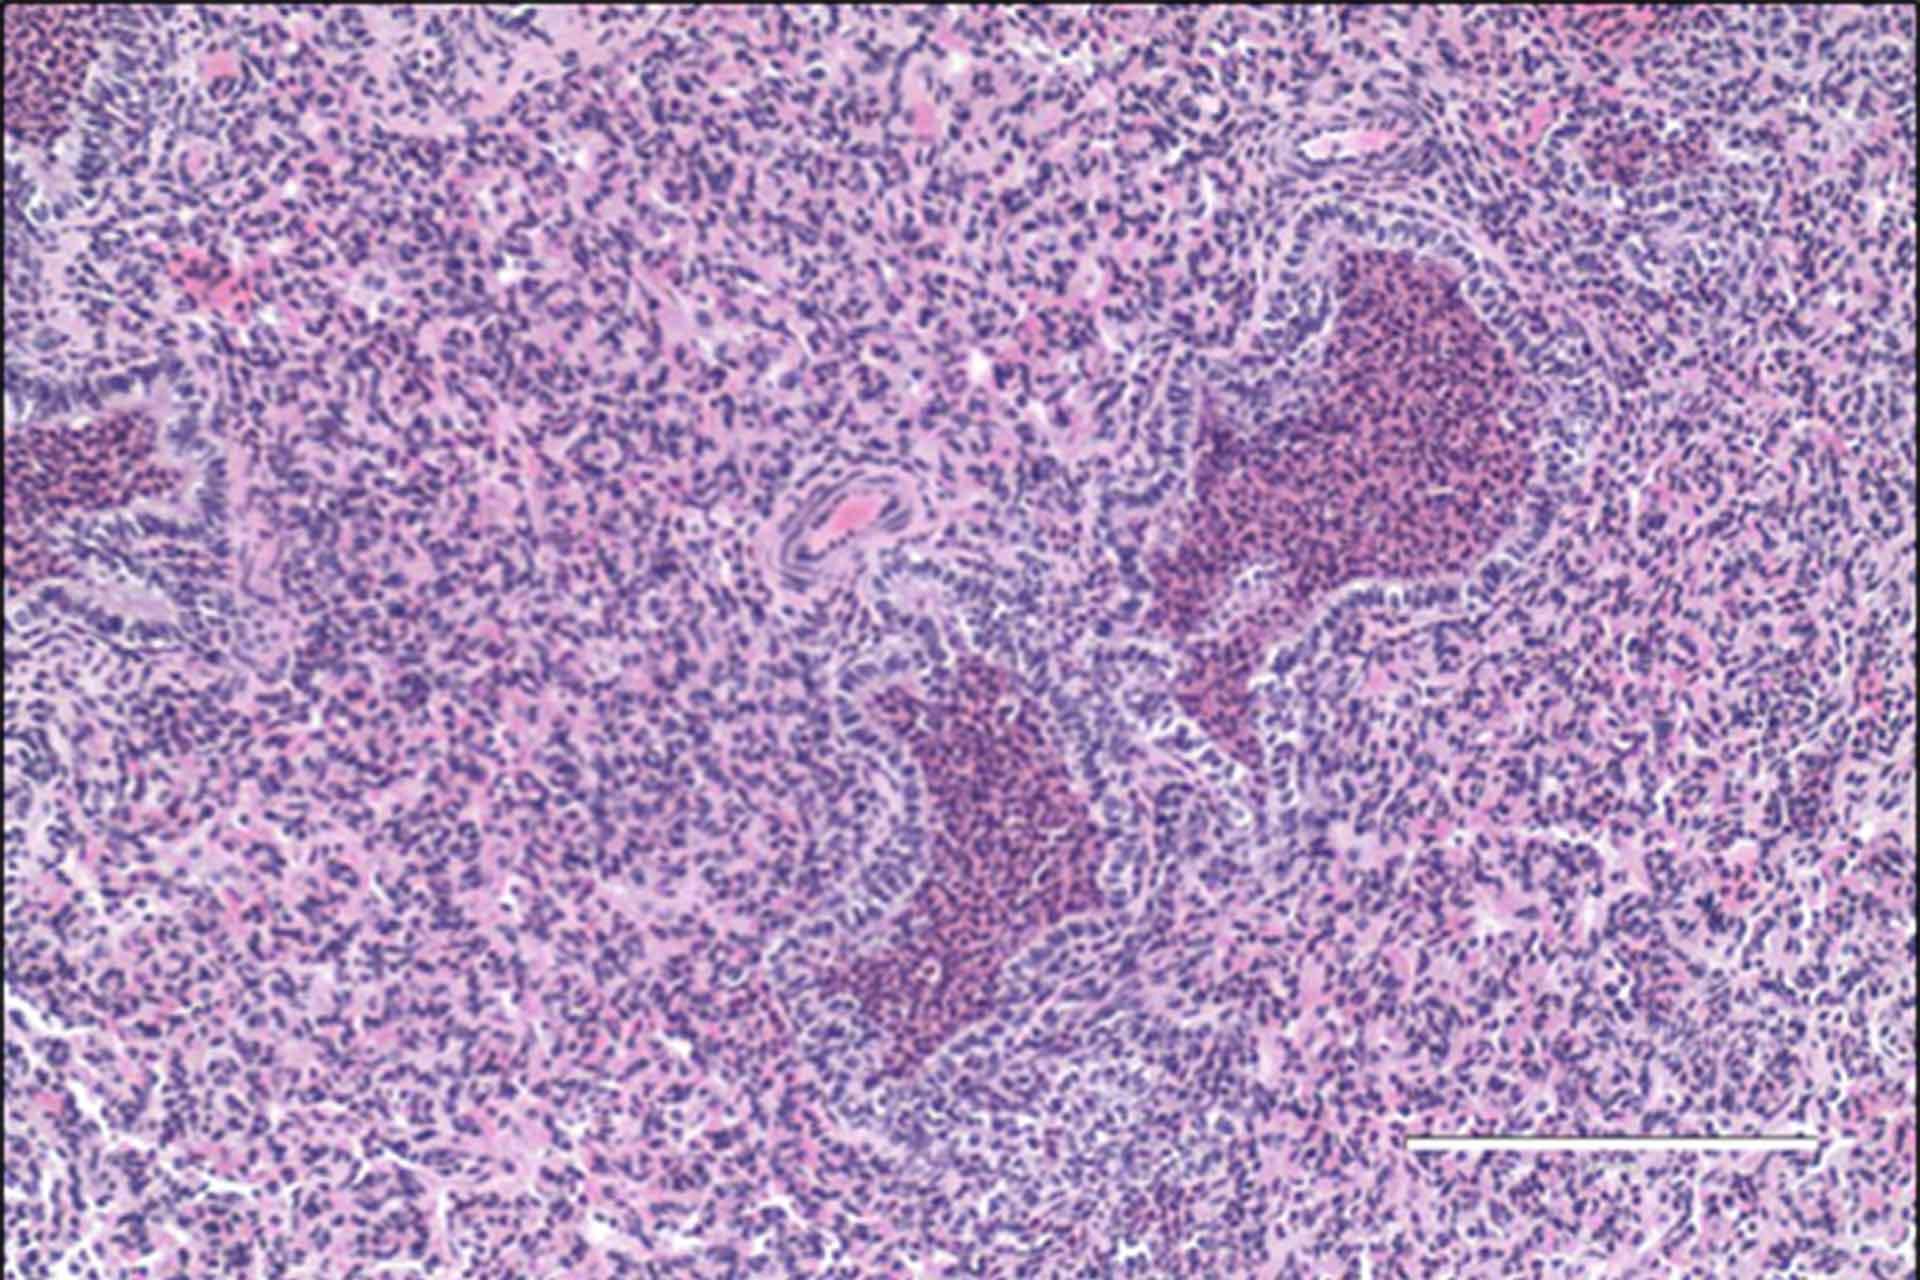

The image is courtesy of Dr Geraldine Taylor and shows a section of lung from a BRSV infected calf showing consolidated lung and bronchioles filled with neutrophils.

Neutrophils are thought to aid the clearance of BRSV and HRSV infections by removing virus infected cells, but when they appear in excessive numbers they seem to have the opposite effect. They release harmful substances that destroy the lung and physically block the airways. The scientists were able to show that large numbers of neutrophils contributed to some of the short term clinical signs associated with BRSV infections such as breathing difficulties.